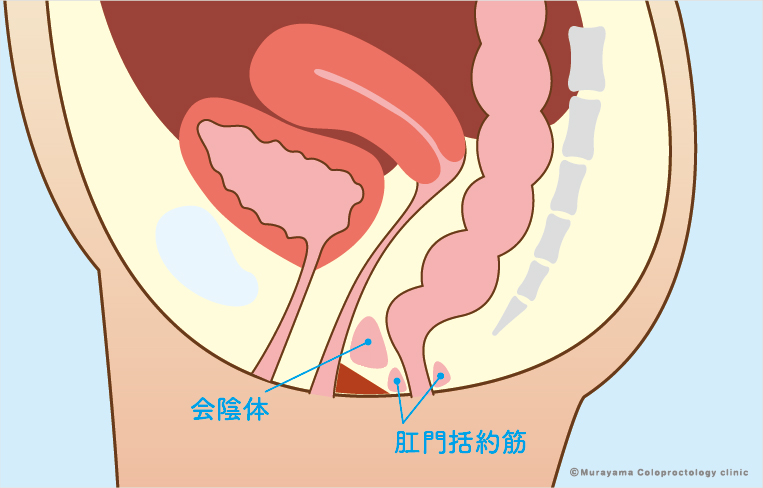

前立腺炎の場合、一般的には会陰部(肛門の前)の鈍痛、 睾丸の鈍痛、排尿痛があげられます。 そして、前立腺炎では多くの場合、この会陰部に痛みが生じます。 会陰部の痛み 急性前立腺炎の場合 急性前立腺炎の場合は、高熱と会陰部痛をともなうため、 男性 会陰部にしこり person 30代/男性 前も相談させて頂きました。 だんなが睾丸のすぐ下から肛門の間にしこりを発見しました。 去年には肛門周囲膿瘍で入院したこともあり、診察を受けに行きましたが、経過は大丈夫で、しこりについては1919 男性 男性の尿道は長く、外尿道口から入った細菌は、膀胱に達する前に排尿によって流されることが多い。前立腺からの分泌液には、細菌の侵入を防ぐ働きがある。 女性 女性は、男性に比べて、尿道が短い上、肛門や膣前庭部と外尿道口が近いので、その分、細菌が膀胱の中に入りやすい。

会陰 ( えいん )とは、 解剖学 において、狭義では 外陰部 と 肛門 の間、広義では左右の 大腿 と 臀部 で囲まれる 骨盤 の出口全体をさす。 恥骨結合 と左右の 坐骨結節 、 尾骨 を結ぶ菱形部となる。会陰と残尿感の解消には、 一体どのような関係性があるのでしょうか。 男性は蟻の門渡りを押すことで残尿感を解消できるのか? 排尿を終えた直後なのに「まだ膀胱内に尿が残っているような気がする、 なんだかスッキリしない」という不快感を覚える 男性の陰部のかゆみの原因として考えられる疾患とは? 男性の陰部にかゆみの症状があるとき、大まかな原因としては「性感染症」「皮膚疾患」の2つの場合が考えられます。 かゆみのある性感染症としては「性器ヘルペス・尖圭コンジローマ・梅毒」などがあり、どれも性行為により感染する可能性があります。 性器ヘルペスでは、陰部に水膨れができ

会陰部 広義の会陰の定義 (会陰部も参照) 前方の陰丘、外側の大腿内側面、後方の殿溝と殿間裂の上縁に挟まれた菱形の領域 (M) 狭義の会陰の定義 男性の場合尿道と会陰の間、女性の場合膣と肛門の間を指す (KH237) WordNet the general region between the anus and the男性の会陰は前後径5~6センチメートル、女性では2~3センチメートルである。 この部分の皮膚の正中線には色素に富んだ会陰縫線 (ほうせん)があり、男性では陰嚢縫線に続く。 会陰部皮下には脂肪組織、平滑筋線維が多く存在し、その深部には横紋筋からなる会陰筋層がある。 骨盤腔 (こう)を上方からみると、骨盤下口を会陰筋が筋膜、腱膜 (けんまく)とともに会陰部のヘルニアについて情報をまとめました。 ヘルニア治療辞典 男性と女性では、起こる場所が異なると言われていますが、女性の方がかかる率が高くなっています。 恐らく、女性は妊娠や出産などがあるため、会陰部が大きく収縮することが原因の1つではないかと考えられます。